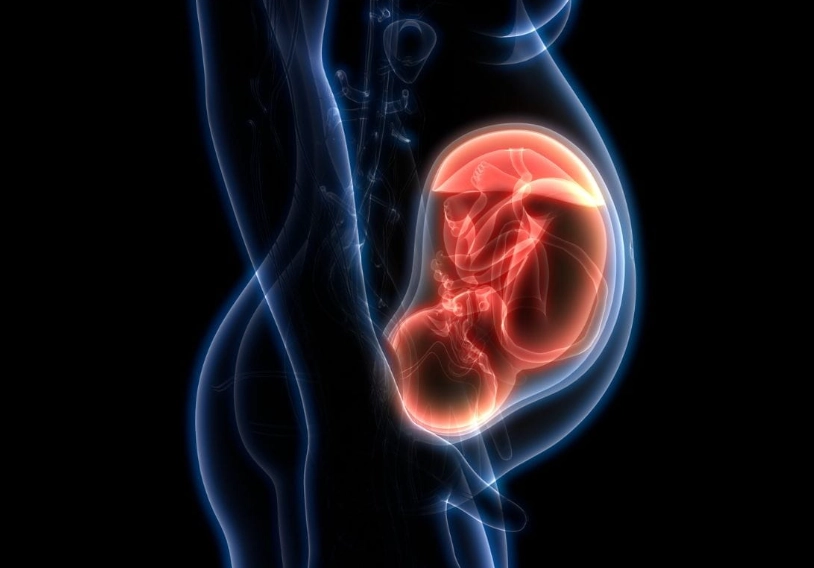

So, where is the baby located in 12 weeks? Picture your uterus. For the first trimester, it's been a pelvic organ, snug behind your pubic bone. At around 12 weeks, it's grown large enough that the top part (the fundus) begins to rise up out of the pelvis and into your lower abdomen. Your baby is inside that uterus, floating in amniotic fluid. It's still relatively low, but it's beginning its journey upward as your uterus expands to make room.

Key Takeaway: At 12 weeks, your baby is transitioning from being solely a "pelvic" resident to becoming an "abdominal" one. You likely won't feel this movement yet, but your uterus is making space.